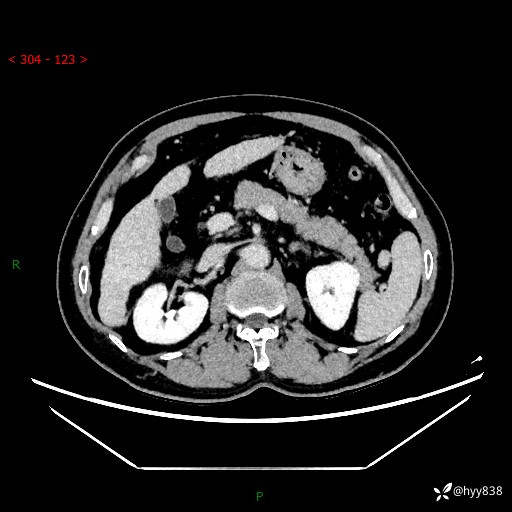

肝脏CT平扫

增强动脉期

静脉期

延迟期